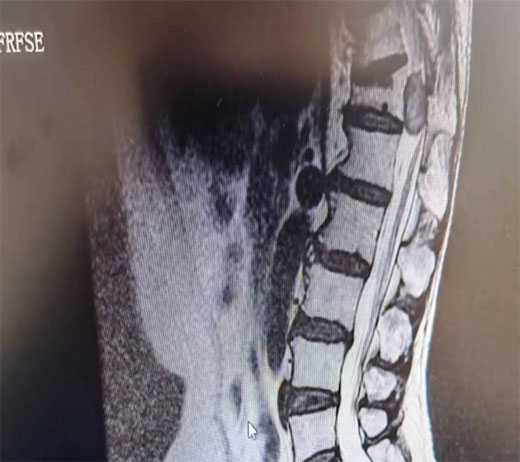

术前资料

该患者曾到多家医院就诊,当椎间盘突出或腓总神经损伤治疗,针灸理疗、拔罐、吃药都不见好转,遂到我科就诊住院。我科经讨论后认为,有可能是椎管内占位,遂给予核磁检查,果真发现胸12椎管内有一“胡豆”大的肿瘤,椎管内位置狭小,脊髓已严重受压,已出院不全瘫痪症状,情况十分危急,必须行肿瘤切除手术。经骨伤科和医院相关科室专家讨论,认为手术风险巨大,很可能出现手术后神经症状加重,甚至导致完全瘫痪,而我院并无相关处理经验,仅多年前请上级医院专家做过类似手术,故建议患者转上级医院或请省里的专家来院做手术。而患者家庭贫困,听说要转院或请专家来做手术,花费比较大,要求出院放弃治疗。患者说:“我都快七十岁了,治好了也挣不了那些钱,回去了养养能好就好,不能好就这样了”。骆渊城副院长得知相关情况后,再次组织科内讨论,一致认为,不做手术必将瘫痪,放手一搏还有希望。遂与患者沟通后决定就在骨伤科手术,并成功在显微镜下完整切除了肿瘤。